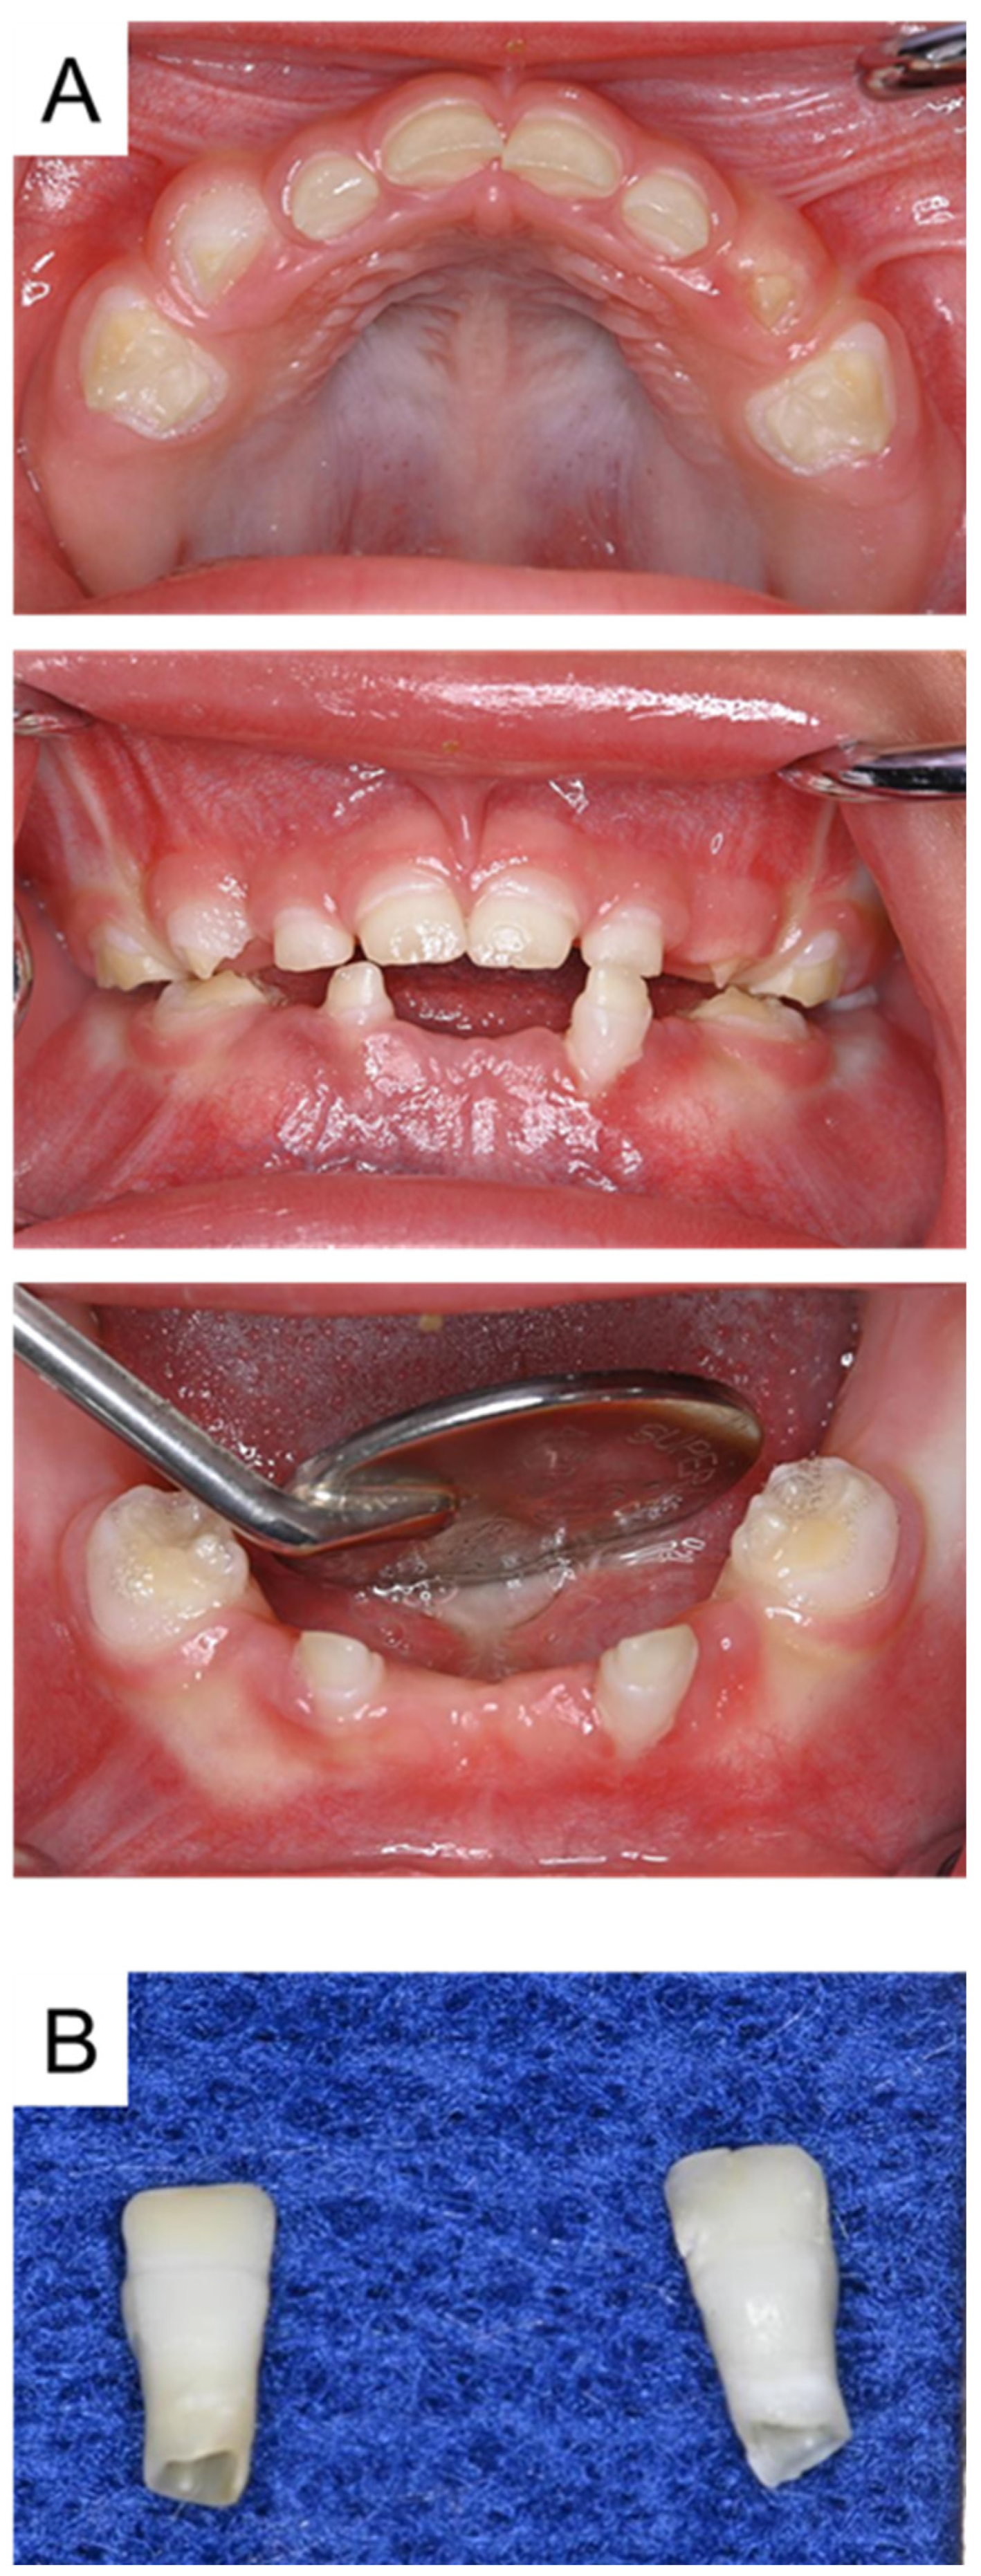

| Tooth | Time |

|---|---|

| Mandibular left primary central incisor | 1 year and 3 months |

| Mandibular right primary central incisor | 1 year and 7 months |

| Mandibular left primary lateral incisor | 2 years |

| Mandibular right primary lateral incisor | 2 years and 4 months |

| Maxillary right primary canine | 2 years and 7 months |

| Mandibular right primary canine | 2 years and 8 months |

| Maxillary right primary central incisor | 3 years |

| Maxillary left primary canine | 3 years |

| Maxillary left primary central incisor | 3 years and 9 months |

| Mandibular left primary canine | 4 years and 3 months |

| Maxillary left primary lateral incisor | 4 years and 6 months |